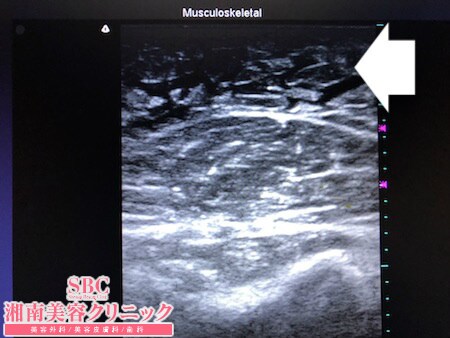

No.245075【脂肪吸引】【動画あり】湘南美容外科脂肪吸引最高責任者である竹田先生による脂肪吸引のフォトギャラリー!顔の整形が終わったので今度は上半身の脂肪吸引を受ける!二の腕術中術中3Dタッチビュー・左ちからこぶ

今回は二の腕の脂肪吸引を受けてくださいましたので

その術中変化を見ていただくことにしましょう。

痩せ型の患者様ですが

二の腕の皮下脂肪が体型の割には

付いているほうでした。

そして皮下脂肪の質が非常に柔らかい。

このような状態は脂肪吸引に向いている

と考えられているので

今後の経過が非常に楽しみです。